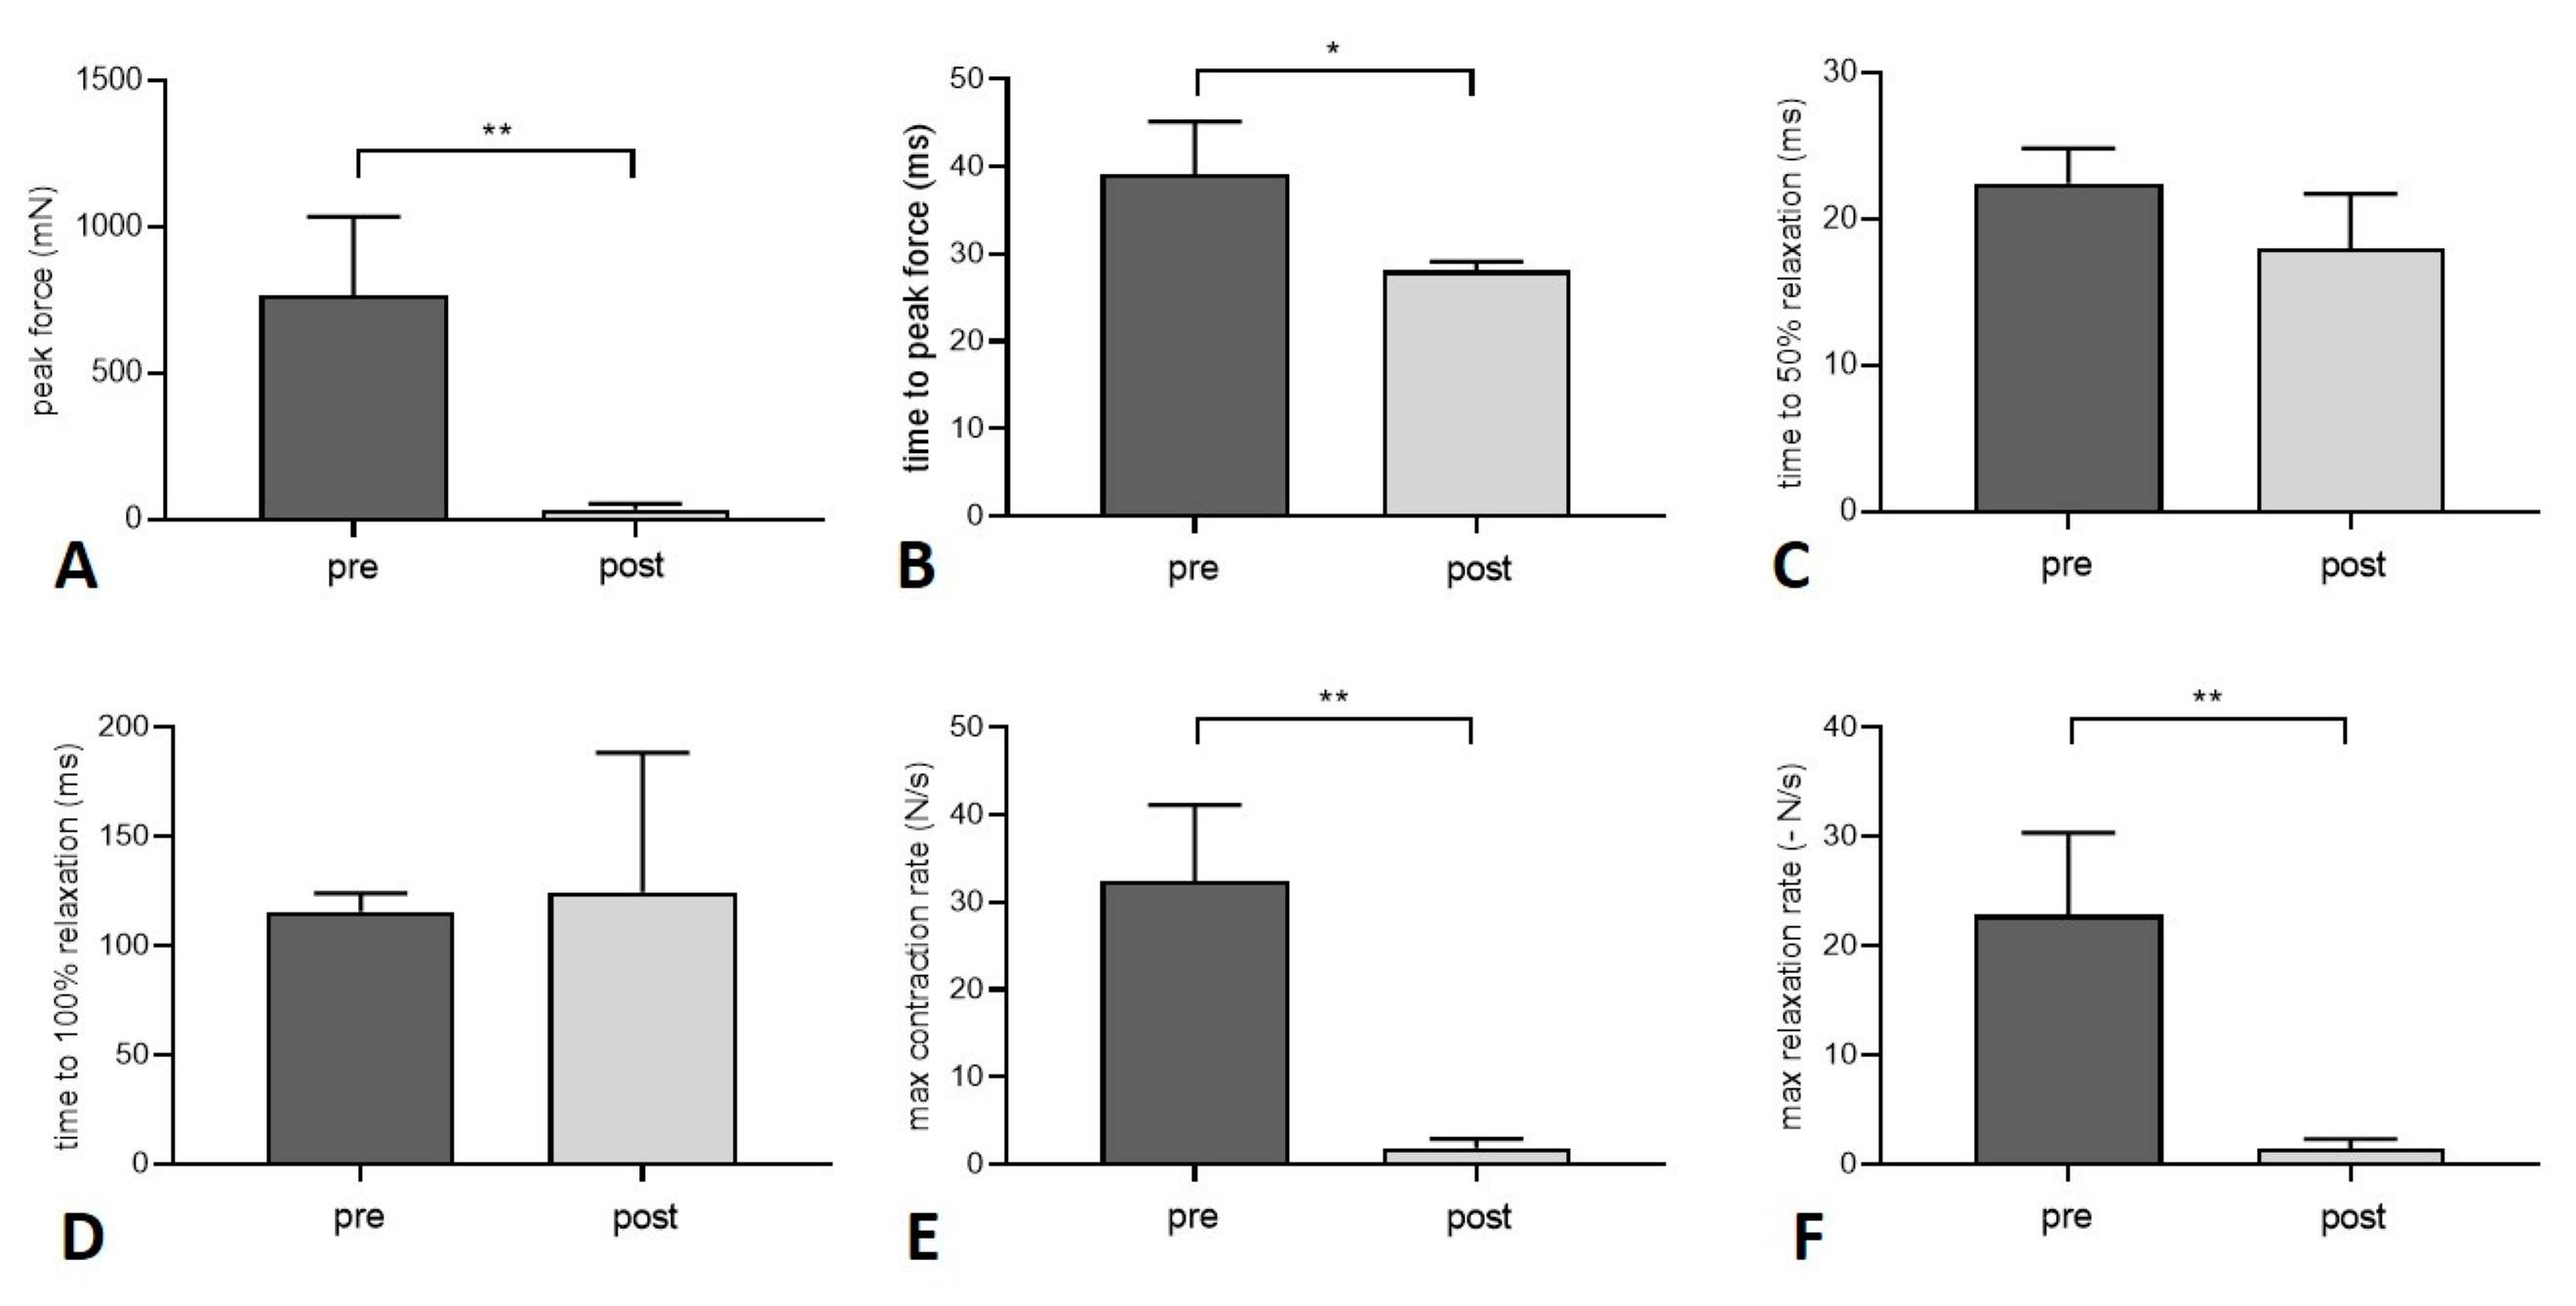

3.2. Muscle Function

| Pre Transplantation | Post Transplantation | |

|---|---|---|

| Peak twitch force (mN) | 768.5 ± 266.6 | 34.7 ± 19.7 (**) |

| Time to peak twitch force (ms) | 39.2 ± 6.0 | 28.1 ± 1.0 (*) |

| Time to 50% relaxation (twitch force) (ms) | 22.5 ± 2.4 | 18.0 ± 3.7 |

| Time to 100% relaxation (twitch force) (ms) | 115.6 ± 8.3 | 124.5 ± 63.9 |

| Maximum contraction rate (twitch) (N/s) | 32.5 ± 8.6 | 1.9 ± 1.1 (**) |

| Maximum relaxation rate (twitch) (-N/s) | 22.8 ± 7.5 | 1.4 ± 0.9 (**) |

| Maximum tetanic force (at 80 Hz) (mN) | 2771 ± 772.7 | 28.6 ± 14.7 (**) |

| Maximum contraction rate (tetanus at 80 Hz) (N/s) | 57.8 ± 14.7 | 1.0 ± 0.5 (**) |

| Time to peak force (tetanus at 80 Hz) (ms) | 33.7 ± 7.1 | 19.6 ± 2.2 (*) |

| Maximum tetanic force (at 100 Hz) (mN) | 2920 ± 981.9 | 32.1 ± 14.2 (**) |

| Maximum contraction rate (tetanus at 100 Hz) (N/s) | 59.1 ± 10.5 | 1.1 ± 0.5 (***) |

| Time to peak force (tetanus at 100 Hz) (ms) | 32.2 ± 4.6 | 19.7 ± 2.2 (**) |

| Maximum tetanic force (at 120 Hz) (mN) | 2970 ± 1172 | 34.5 ± 13.4 (**) |

| Maximum contraction rate (tetanus at 120 Hz) | 56.3 ± 19.7 | 1.2 ± 0.5 (**) |

| Time to peak force (tetanus at 120 Hz) (ms) | 32.5 ± 2.8 | 19.6 ± 1.9 (***) |